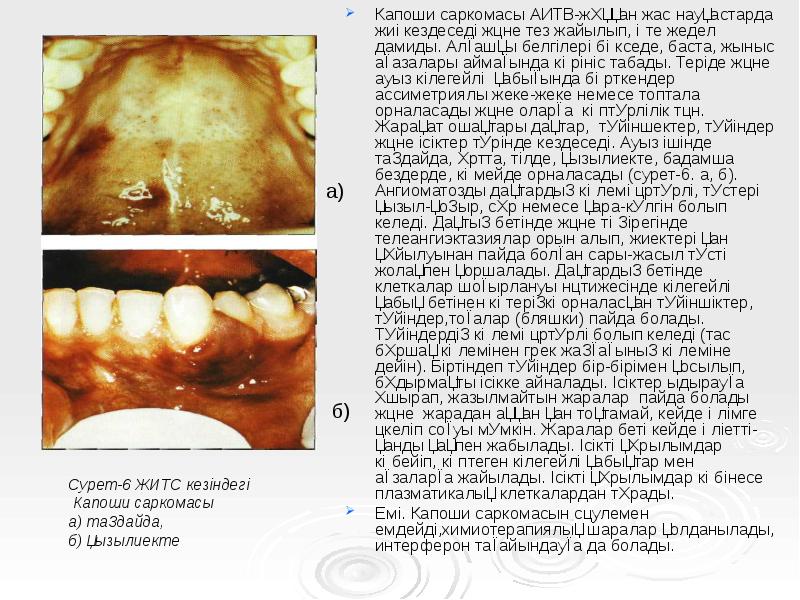

- 62. Капоши саркомасы АИТВ-жұққан жас науқастарда жиі кездеседі және тез жайылып, өте

- 63. Әдебиеттер: Әдебиеттер: Асмагамбетова М.Т Дилдабкеова.Н.Т вирустарға қарсы